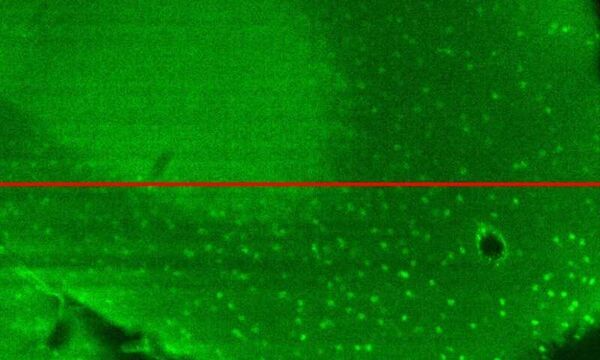

Plug-and-Play Lens Simplifies Adaptive Optics for Microscopy

"Device makes it easy for scientists to access high-quality images from deep inside tissue Researchers have developed a new plug-and-play device that can add adaptive optics correction to commercial optical microscopes. Adaptive optics can greatly improve the quality of images acquired deep into biological samples, but has, until now, been extremely complex to implement. “Improving the technology available to life scientists can further our understanding of biology, which will, in turn, lead to better drugs and therapies available to doctors,” said research team leader, Paolo Pozzi from the University of Modena and Reggio Emilia in Italy. In The Optical Society (OSA) journal Optics Letters, Pozzi and a multidisciplinary team of researchers from Delft University of Technology (TU Delft), CNR-Institute for Photonics and Nanotechnology (CNR-IFL) and University Medical Center Rotterdam describe their new adaptive lens device. They also show how it can be easily installed onto the objective lens of a commercial multiphoton microscope to improve image quality. “This approach will allow advanced optical techniques such as multiphoton microscopy to image deeper under the surface of the brain in live organisms,” said Stefano Bonora, group leader at the CNR-IFL." [...]